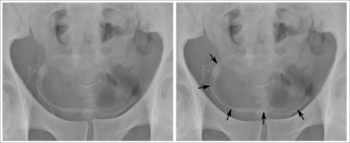

Calcification of the bladder wall on a plain x-ray image of the pelvis, in a 44-year-old sub-Saharan man. This is due to urinary schistosomiasis.

The worms of S. haematobium migrate to the veins around the bladder and ureters.[21] This can lead to blood in the urine 10 to 12 weeks after infection.[14][17] Over time, fibrosis can lead to obstruction of the urinary tract, hydronephrosis and kidney failure.[14][17] Bladder cancer diagnosis and mortality are generally elevated in affected areas, and efforts to control schistosomiasis in Egypt have led to decreases in the bladder cancer rate.[17][23] The risk of bladder cancer appears to be especially high in male smokers, perhaps due to chronic irritation of the bladder lining allowing it to be exposed to carcinogens from smoking.[17][19]